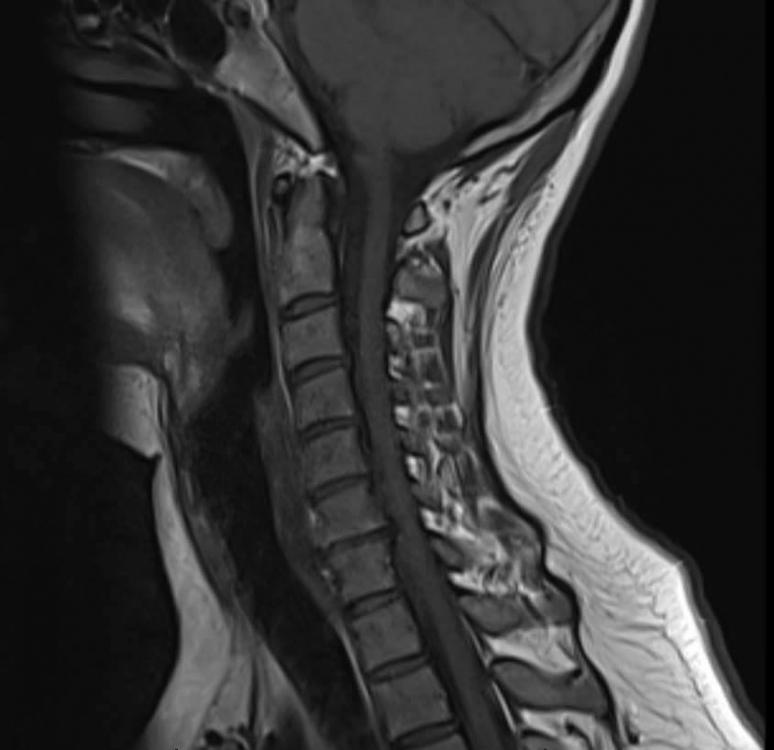

Möglicherweise sind es auch mehr diese Osteochondrosen die auf den Nerv drücken? Ich habe mal zwei MRT Bilder angehängt.

MRT1.jpg

MRT2.jpg

Ich kann dich beruhigen, dein Nerv ist mit Sicherheit nicht abgestorben;) Es ist nämlich so. Dein Nerv wird ebenfalls von kleinen kapillaren versorgt, das sind die kleinsten Blutgefäße. Wird der Nerv so stark gedrückt das seine Versorgung nicht mehr gewährleistet ist wird er nicht nur mit einem krippeln und Taubheitsgefühl reagieren sondern mit Schmerzen. Das wäre eine Bedrohung für den Nerv, und die roten Warnlämpchen (Schmerzen) springen an. Bevor dein Nerv abstirbt würden nach Sensibilitätsstörungen und krippeln, motorische Ausfälle folgen i.Sinne von Kraftidefizit und Lähmungen. Um das zu verstehen muss man wissen wie ein Nerv im Querschnitt aussieht. Im Inneren befinden sich geschützt von den Sensiblen Fasern die Motorischen. Diese Sind dafür zuständig daß wir überhaupt unsere Muskulatur anspannen Können. Um Ihnen liegen wie eine Hülle die Sensiblen Fasern, die für das Gefühl zuständig sind, und auch Schmerzreize die über Rezeptoren ins Gehirn weitergeleitet werden liegen ausen. Das ist sinnvoll. Die motorischen Fasern sind letztendlich viel wichtiger wie die Sensiblen Nervenfasern. Sobald die Hülle komprimiert wird kommt es also zunächst zu krippeln und Taubheitsgefühlen. Geht die Kompression weiter oder ist sie heftig daß sogar Motorische Fasern im Inneren gedrückt werden dann kommen erstmal Schmerzen, meist auch brennende Schmerzen, die diese Gefahr signalisieren. Zum Schluss kommt es dann zu Lähmungen. Trotzdem sollte so schnell wie möglich deine Nervenwurzel entlastet werden. Was deine Therapeutin gemacht hat war eine HWS-traktion. Man zieht die HWS quasi in die länge. Dies kann bei akuten BSV sicherlich für Entlastung sorgen, aber es gibt effekivere Methoden da Der Nervenkanal nur solange erweitert wird wie eine Traktion durchgeführt wird danach ist der Zustand aber wieder wie vorher. Auf dem oberen  MRT bild kann man nun sehr schön deine BSV in den entsprechenden Wirbelsegmenten sehen und deine Beschwerden nachvollziehen. Hier muss unbedingt das ausgetretene BSmaterial wieder zurückgebracht werden. Ich habe bei meinen Pat.gute Erfahrung gemacht mit der Mobilisation der HWS in die Extension (Das ist die überstreckung) der HWS.  Haben deine Therapeuten auch den Nerv mitbehandelt? Dies wäre auch eine wichtige Sache, über sog. N.radialis mobilisation zusätzlich die Nervensymptome zu reduzieren, denn  auch der Nerv der in Mitleidenschaft gezogen ist, muss sich ja wieder regnerieren. Oft ist das NErvensystem noch unflexibel und das NErvengleitlager verklebt. Deshalb sollte 1.die Ursache in der HWS behandelt werden und 2. Eine Symptombehandlung der betroffenen Nerven mit in der Behandlung Eingebunden werden